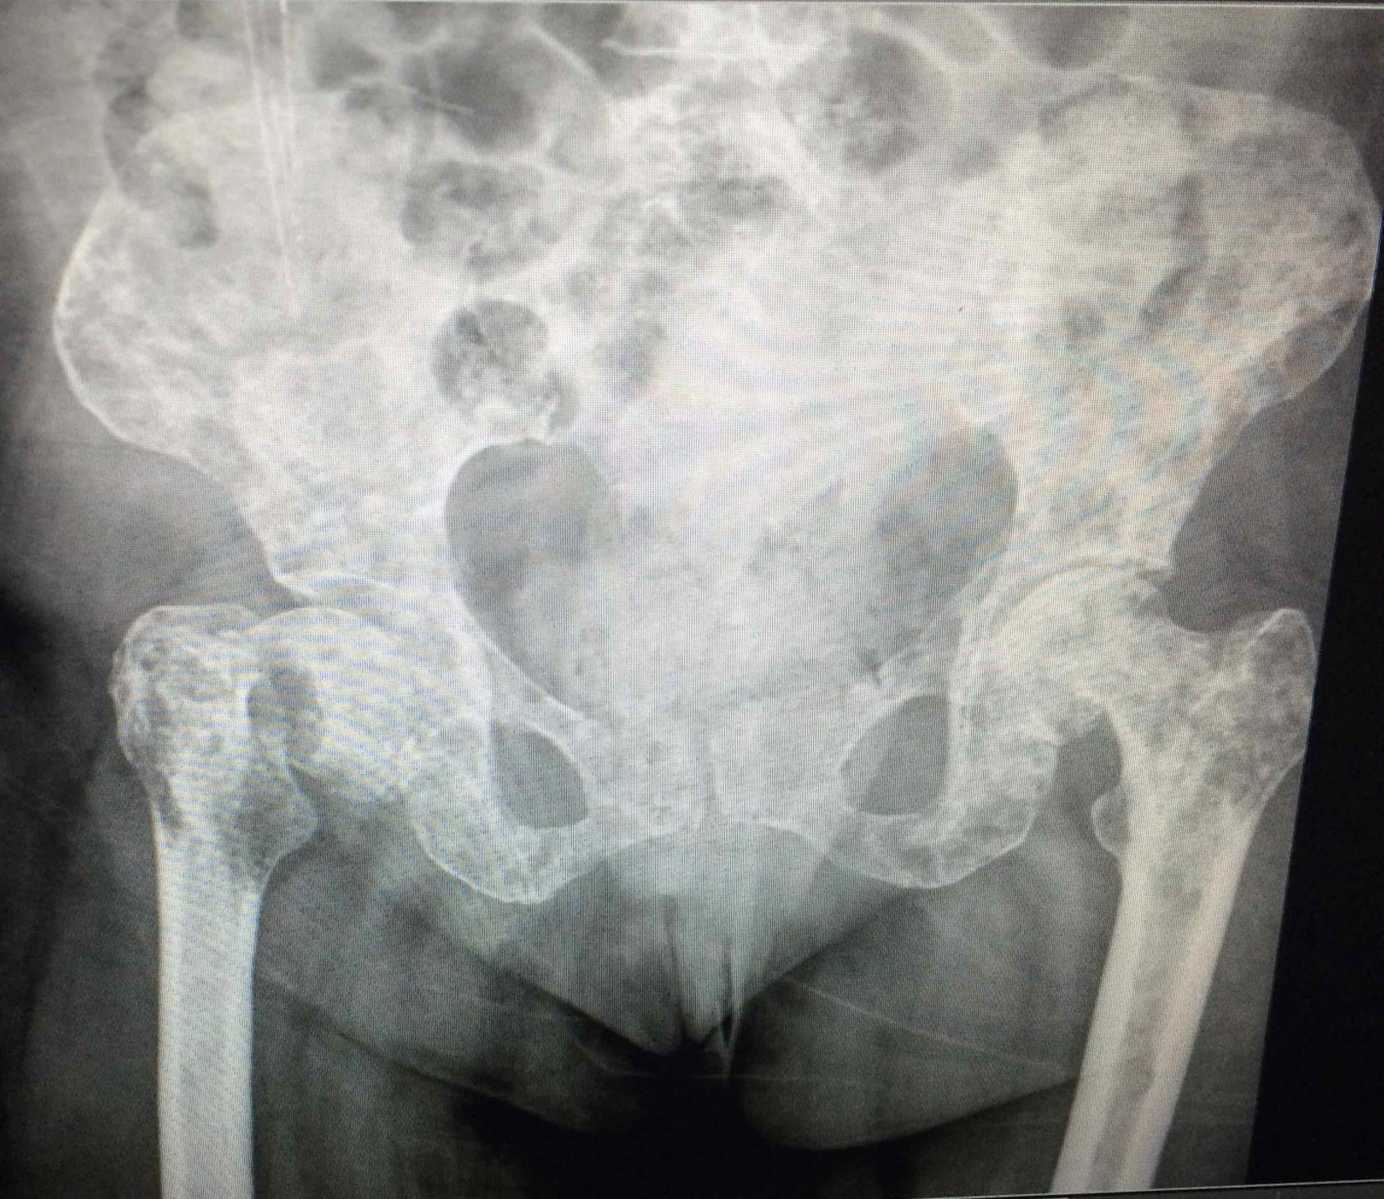

Metástasis óseas trauma .

Enfermedad metastásica ósea: Diagnóstico y tratamiento .

Lesiones tumorales y pseudotumorales del esqueleto ... .

- 4) METSTASIS .

REACCIONES DEL HUESO FRENTE AL ESTRES: ESTUDIO RADIOLOGICO .